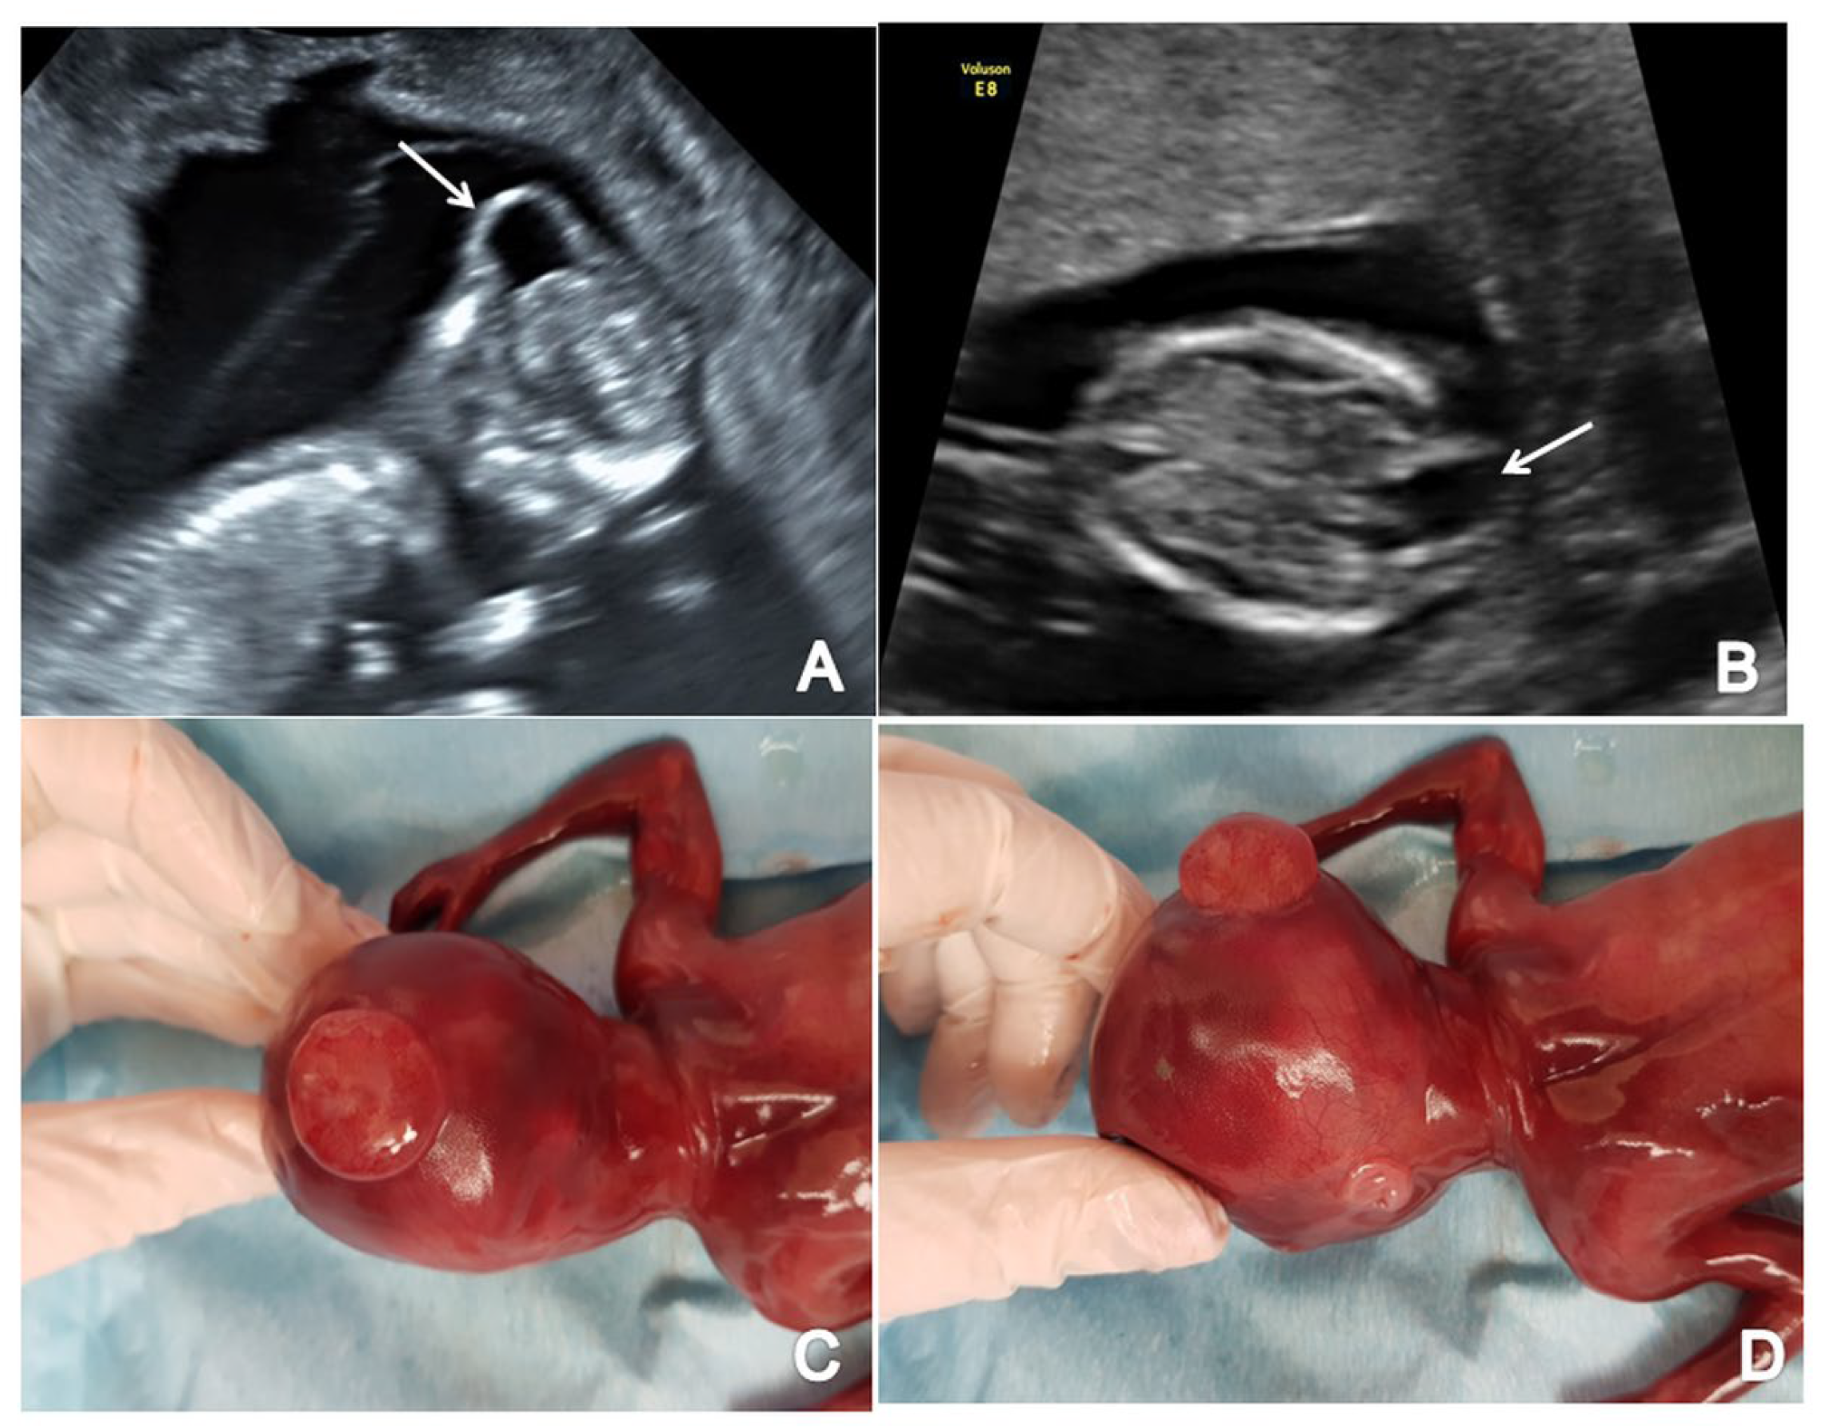

3.6. Ventriculomegaly/Hydrocephaly

The single case of hydrocephaly was diagnosed due to enlarged lateral ventricles relative to the choroid plexus and increased third ventricle, IT and CM. We noted an abnormal sagittal view with an important disproportion between the head and the rest of the body (Figure 8).

Figure 8.

First-trimester ultrasound images of a fetus with hydrocephaly (Case 11): (A) enlarged cerebral ventricles with shrinked choroid plexus (axial view); (B) increased third ventricle (axial view); (C) abnormal sagittal view with increased forth ventricle and cisterna magna (arrow); (D) sagittal view with an important disproportion between head and body and frontal bossing (arrow).